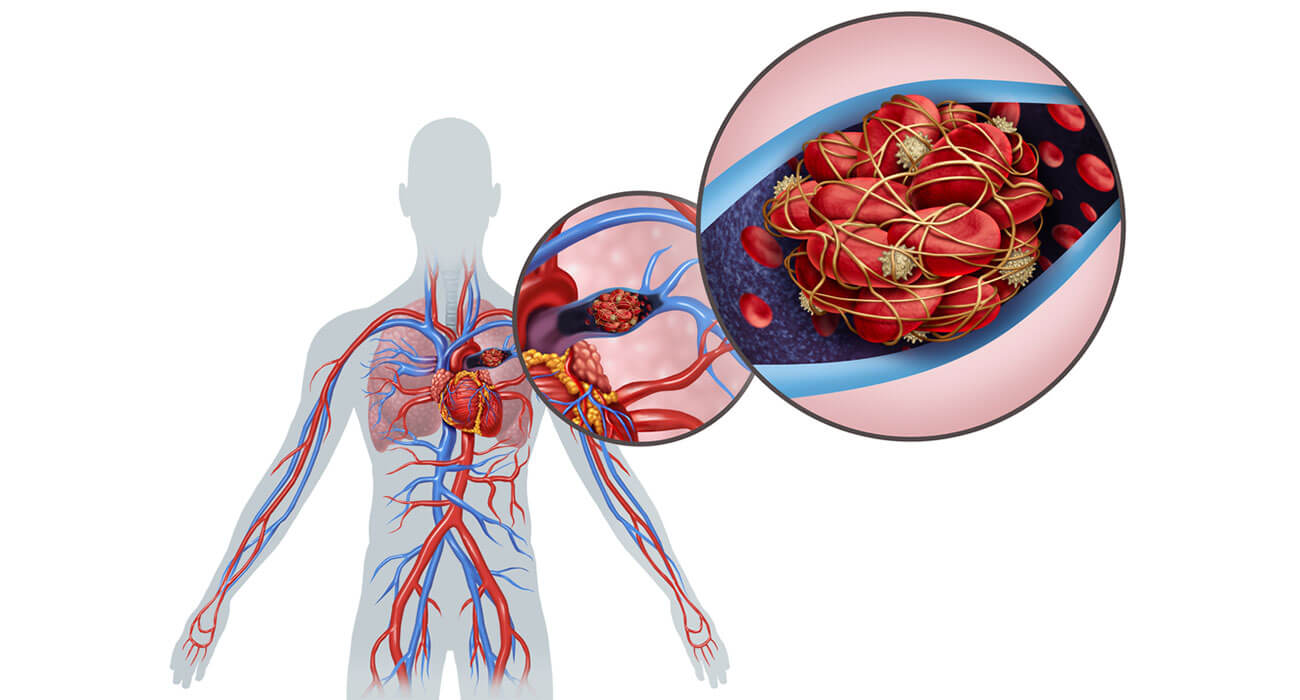

What is Pulmonary Embolism? A Pulmonary Embolism occurs when a blood clot in one part of the body (often in the arm or leg) travels through the bloodstream and becomes lodged in the blood vessels of the lung. When a clot forms in a vein and stays there, it is called a thrombus; when it breaks free from the vein’s…